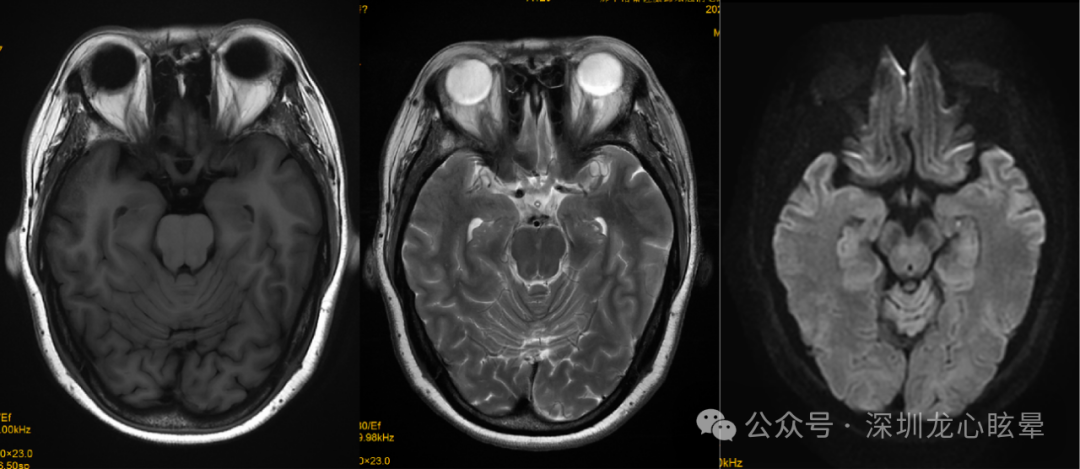

脑干病变引起血管源性头晕/眩晕:支配眼动与姿势平衡的神经整合中枢及传导束主要位于延髓背侧、脑桥被盖与中脑顶盖等区域。这一区域血供丰富,来自延髓外侧动脉、AICA、PICA的诸多分支在此形成吻合支,单纯的小梗死灶在临床较为少见,但该区局限性小梗死灶一旦出现,临床上常以类似前庭神经炎的症状就诊。脑干区域虽较为狭小,但重要核团众多,与人体平衡感知、前庭眼动反射相关的诸多核团均位于该区,如前庭神经核群、第8颅神经在脑桥延髓交界处出入脑干段区、眼动控制核团(如舌下神经前置核、Roller核、闰核、旁中央束细胞组)等,上述部位病变除了引起头晕、眩晕及失衡症状外,通常伴随邻近结构损害相关症状和体征,需重视神经系统查体以及脑干综合征的识别(延髓背外侧综合征、延髓内侧综合征、脑桥被盖下部综合征、核间性眼肌麻痹等)。若病变仅损害延髓-脑桥背侧的前庭神经核、舌下周核复合体或第Ⅷ对脑神经延髓-脑桥交界入颅段可表现为中枢性血管源性头晕/眩晕,其中 REZ区域因供血动脉吻合支丰富,梗死较为罕见。

图3 一例右侧延髓急性脑梗死(椎动脉夹层)

图4 一例延髓海绵状血管瘤

(5)孤立性前庭神经核梗死:前庭神经核是一组核团,包含内侧核、外侧核、上核、下核4部分,其中位于脑桥下部的4个核团由 AICA 供应,而位于延髓上部的前庭神经内侧核和下核由 PICA 供应。前庭神经核受损可能同时表现为外周和中枢前庭病变的特征,使诊断极具挑战性。可表现类似前庭神经炎的孤立性眩晕,朝向健侧的水平-扭转自发眼震,固视可抑制,去除固视眼震增强,患侧水平 HIT及双温试验阳性、患侧前庭肌源性诱发电位减低或引不出,早期头颅 MRI正常。但同时患者又表现出凝视诱发的变向眼震(中枢前庭受损的表现),显示神经整合器功能障碍(水平眼动的神经整合是由前庭内侧核、舌下神经前置核和绒球共同完成)。患者复查头颅 MRI显示单侧前庭神经内侧核和下核梗死。

(6)孤立性 NPH 梗死 : NPH 由来自基底动脉的穿支动脉及来自盲孔浅动脉的前内侧长动脉供应。NPH 与前庭内侧核、内侧纵束、旁正中网状结构相邻,是水平眼动的神经整合器,参与视动通路,协调头部和躯干运动。孤立性 NPH 受损常表现为朝向患侧的自发眼震;GEN(在注视患侧时眼震增强)。患侧扫视正常,但平稳跟踪异常;床旁 HIT 阴性,双温试验正常。可向健侧倾倒。